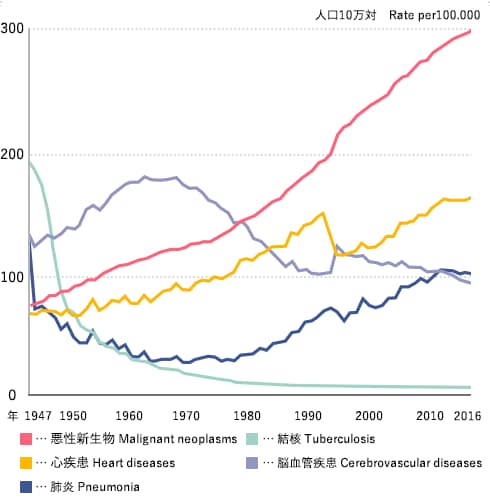

主要死因別粗死亡率年次推移(1947年~2016年)

日本における死亡率の年次推移を死因別にみると、明治から昭和初期まで多かった結核、肺炎などの感染症が第2次世界大戦後急速に減少し、かわっていわゆる生活習慣病(がん、心疾患、脳血管疾患など)による死亡が上位を占めるようになりました。

近年は人口の高齢化の影響により、肺炎が脳血管疾患にかわり死因の第3位になっています。

がん(悪性新生物)は昭和56(1981)年から死因の第1位を占め、平成28(2016)年には37万2986人、人口10万対死亡率298.3であり、総死亡の28.5%を占めています。